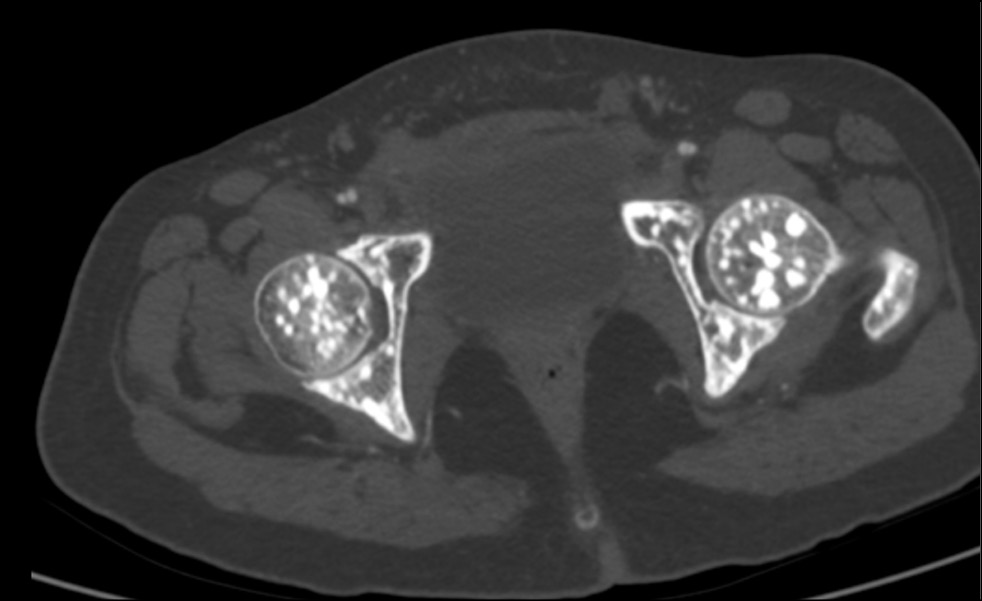

A 43-year-old female patient was taken to the emergency room by ambulance after experiencing transient loss of consciousness. The initial evaluation consisting of history, physical examination, 12-lead electrocardiogram and laboratory tests did not reveal any abnormalities; thus, a total-body computed tomography (CT) was performed. The CT scan showed multiple small sclerotic foci bone islands, scattered throughout the thoracic (Figure 1a) and lumbar spine (Fig. 1b), ribs, pelvic bone (Fig. 2), sacrum (Fig. 3) and bilateral proximal femur (Fig. 4). All bones were free of any cortical erosion or periosteal reaction. No other signs, such as rubor or edema, were noticed; moreover, the patient did not describe any numbness, tingling and weakness in the legs or other parts of the body.

Fig. 1. Transverse cross-section computed tomography scan passing through the thoracic (a) and lumbar (b) spine. It shows numerous, well-defined, homogeneous, circular, hyperdense foci in spinous processes and vertebral arches.

Fig. 4. Transverse cross-section computed tomography scan passing through the femoral head. It shows numerous hyperdense lesions that conform with the osteopoikilosis in the femoral head; lesions are well-circumscribed and are measured in millimeters.